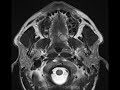

Palatal Basal Cell Carcinoma

T1 mildly hypointense, STIR hyperintense, enhancing mass in the left soft palate which demonstrates mild restricted diffusion compatible with hypercellularity. There is no evidence of perineural spread into the palatine foramina. Differential considerations include a minor salivary gland tumor such as adenoid cystic carcinoma, squamous cell carcinoma, or metastasis. Biopsy revealed this mass to be basal cell carcinoma of the minor salivary glands, a rare entity. The patient subsequently underwent resection of the mass.